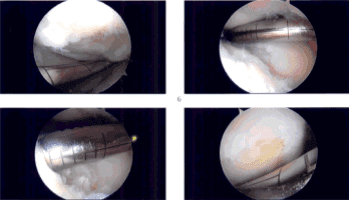

Había un defecto de grado IV en el cóndilo femoral medial que se desbridó con curette y desbridó, y se realizó condroplastia por abrasión con curette. El defecto fue medido y medía 1,5 cm por 1,5 cm. El examen reveló un ligamento cruzado anterior intacto.

El examen señaló que el compartimento patelofemoral del tendón tibial lateral mostró cartílago intacto. El examen del compartimento patelofemoral mostró cartílago intacto sobre la rótula, pero había una lesión osteocondral de grado III a IV de la troclea.

El desbridamiento de esta lesión se realizó hasta márgenes estables. El defecto se midió en 1,5 cm x 1 cm. Se tomaron todas las mediciones. Todas las fotos fueron tomadas y guardadas.

Imágenes de artroscopia intraoperatoria